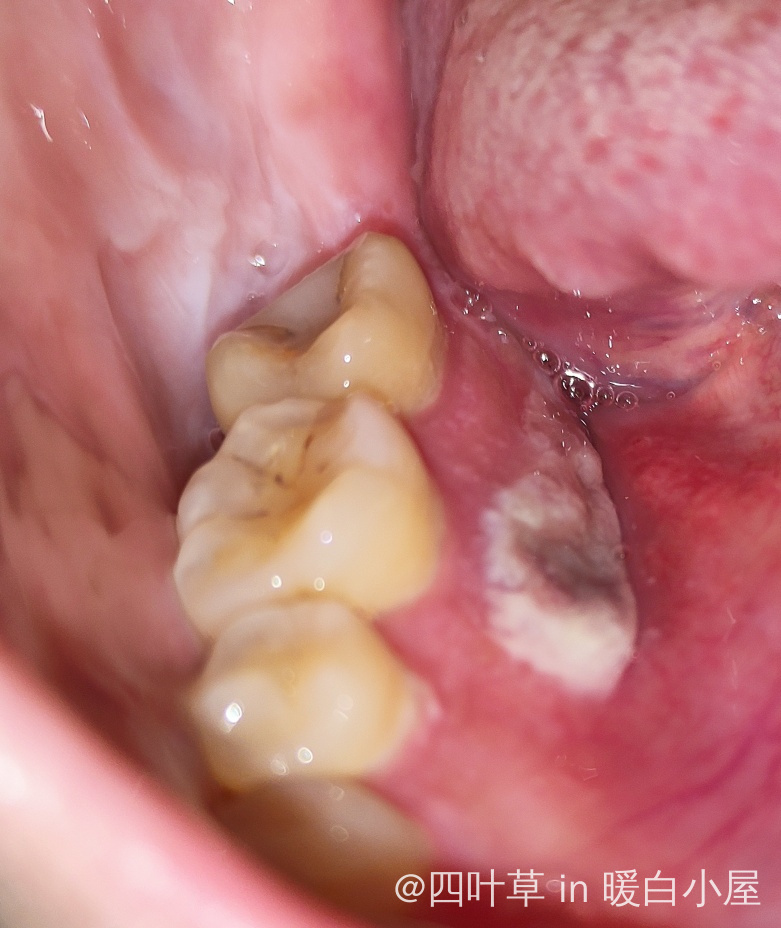

第四天,第一天和第二天是扁平的白色感觉口腔那层膜不规则破损,前面吃饭那些触碰也不疼,第三天开始突起来了,现在溃烂面积加大了,半个嘴巴都难受,酸爽,扯着头和脸颊骨都疼,再不快快好起来就要做活检了排除口腔癌病变,有这样的吗?出来聊聊,相互交流

你这是口排,亲,扁平苔癣,慢慢熬,吃清淡一些了

我这个过了两天其他部位又长出疱疹了,现在医生按疱疹来治疗的